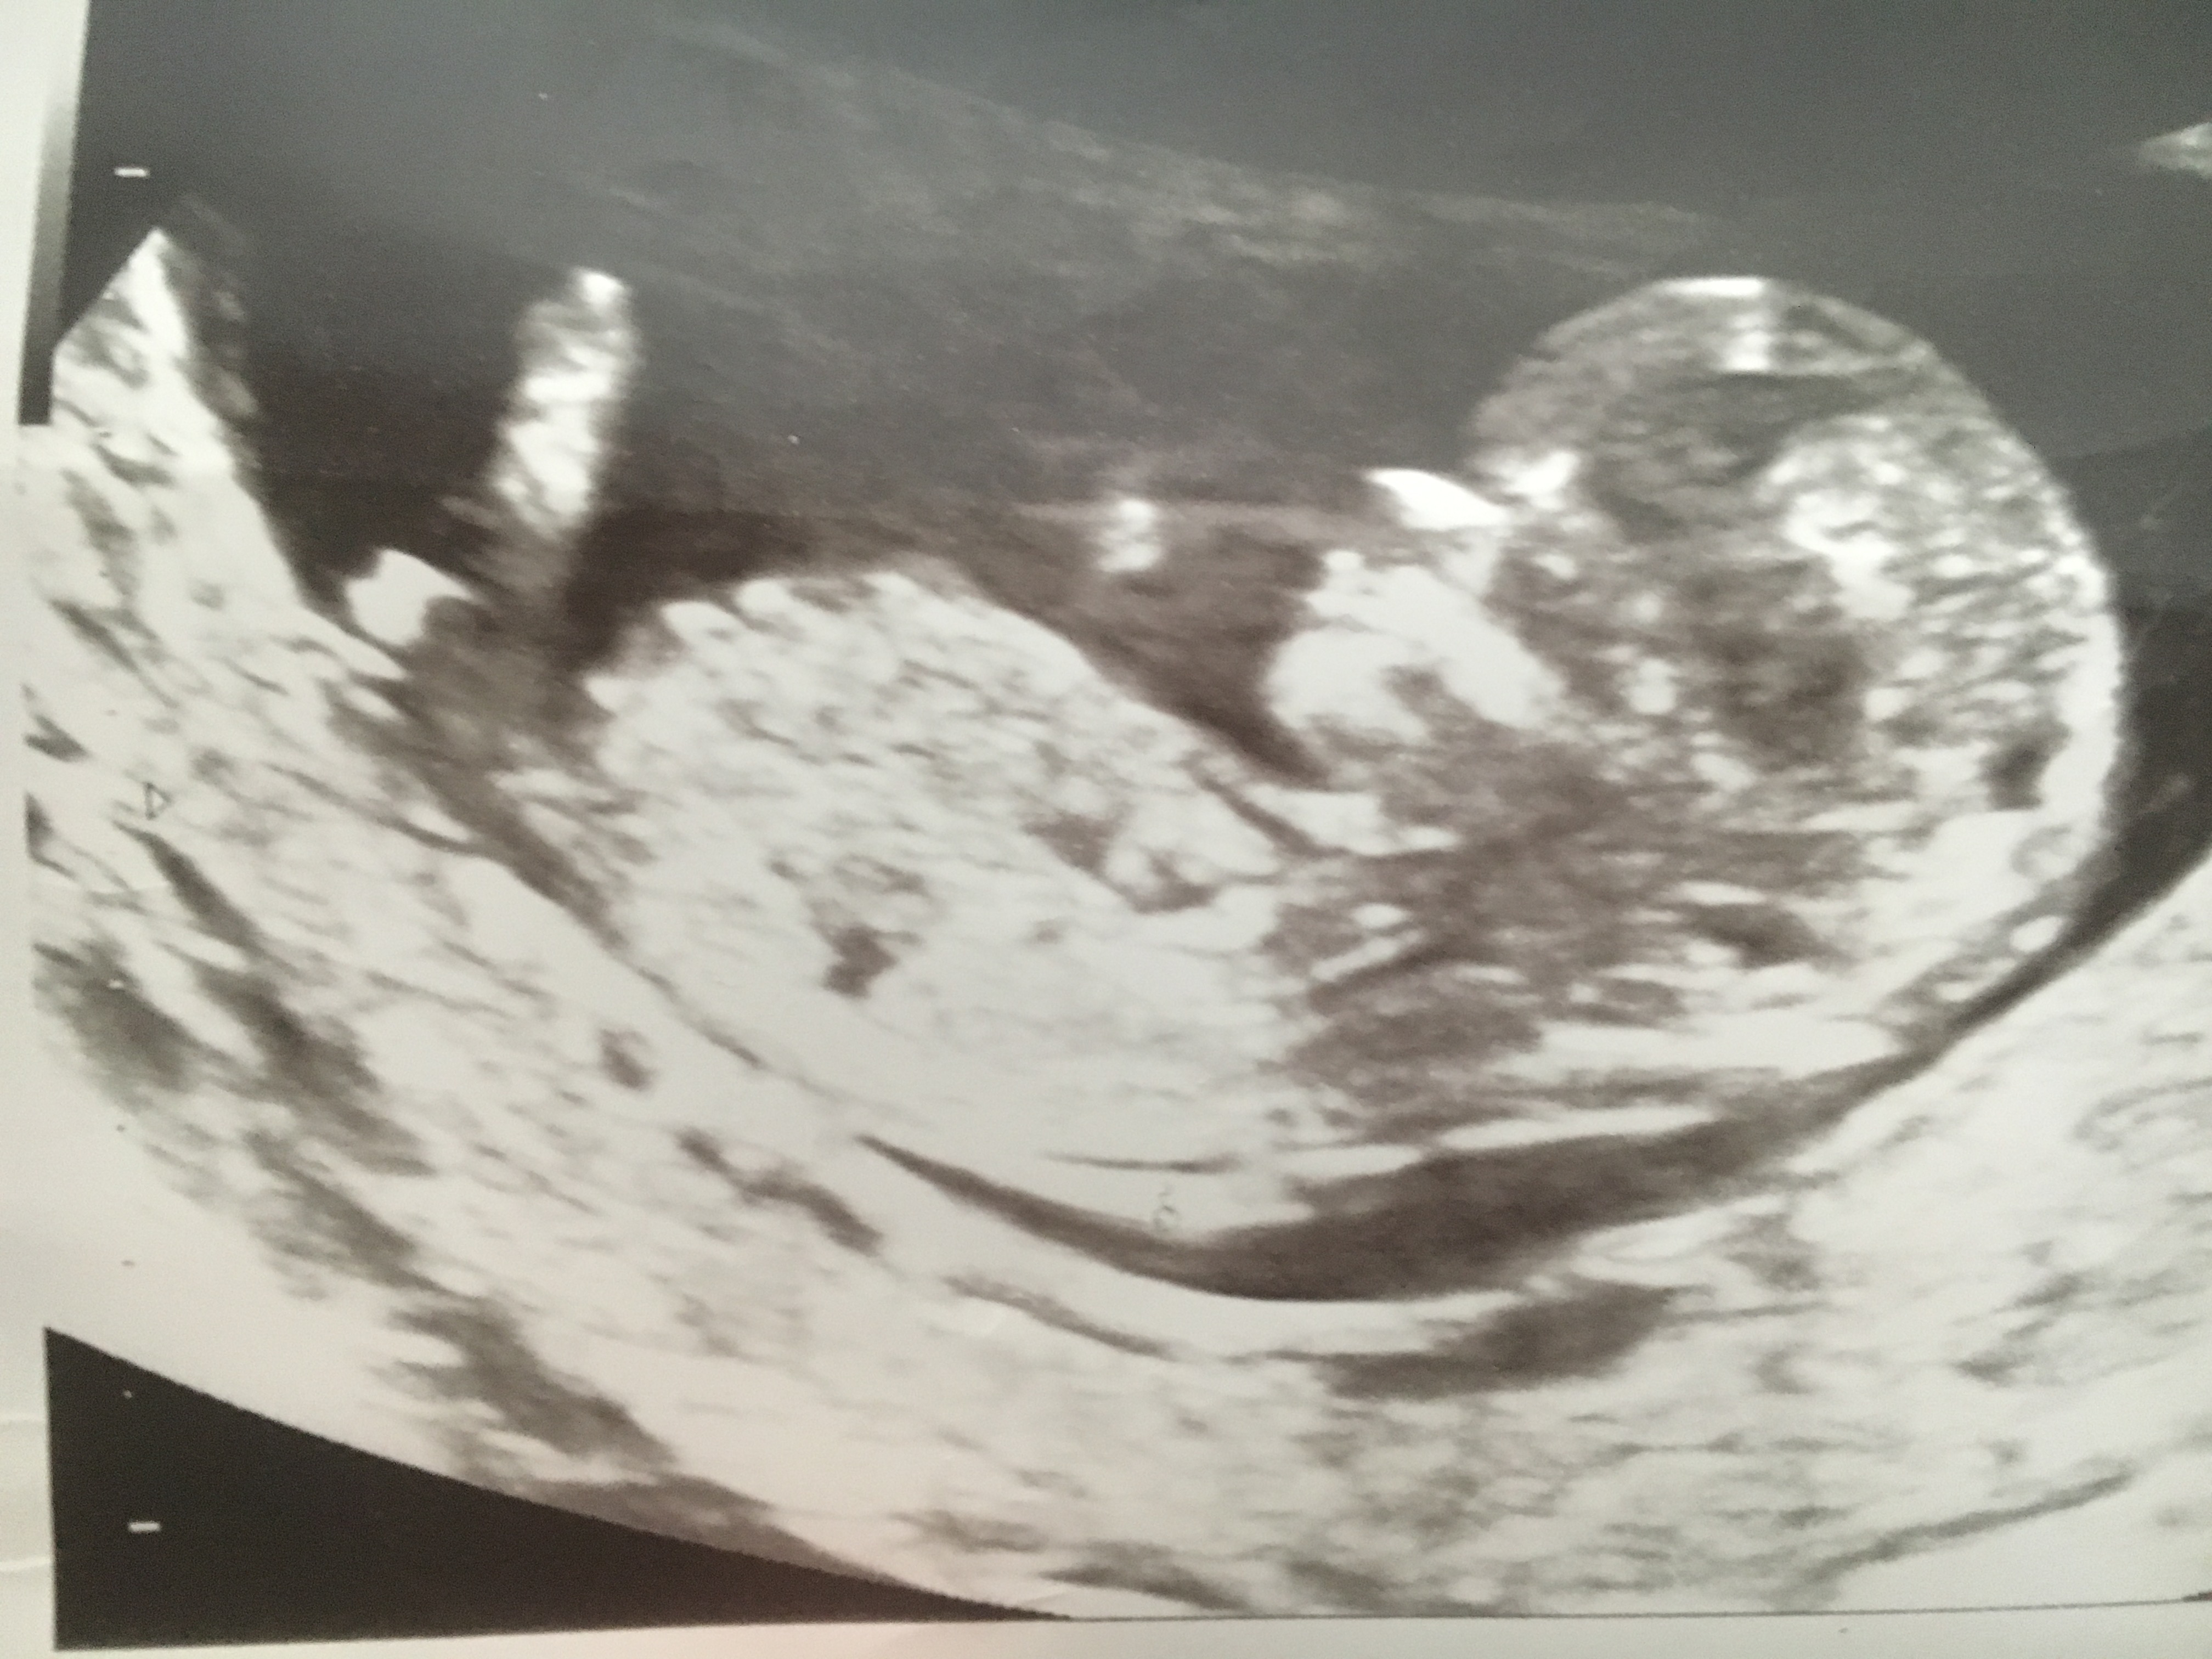

Scan done at 12 weeks 6 days

Looks awfully boy like to me, feeling quite deflated as this is our final baby and will be boy # 5. Should I hold onto any glimmer of hope??

I don't think this shot is good for guessing. I feel like they have focused in on the wrong spot in this one. I'll take a look at the other one

BTW if you think that huge thing sticking up is a penis, it isn't!